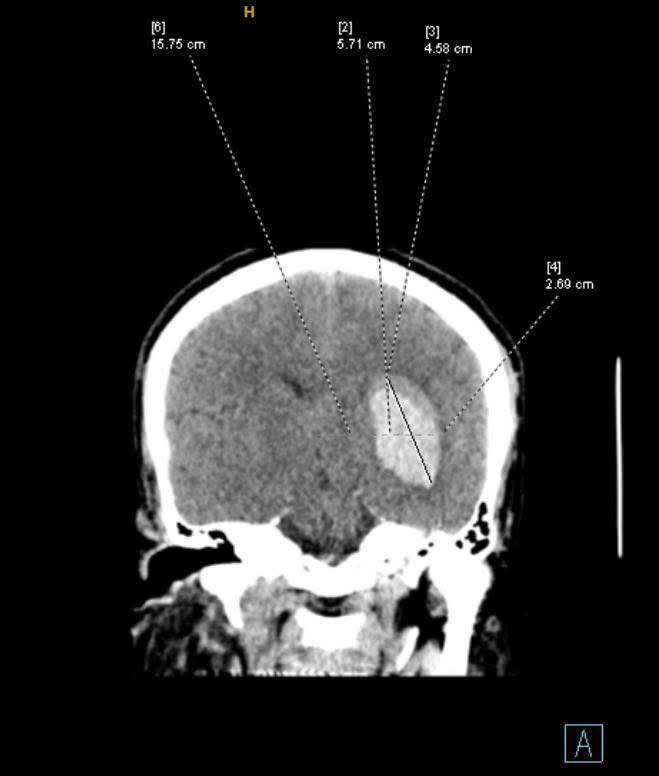

Một trường hợp cấp cứu đột quỵ của bác sĩ Nguyễn Thắng Nhật Tuệ vì bệnh nhân thường xuyên bỏ thuốc huyết áp. (Nguồn ảnh: Page “Một ngày ở viện”)